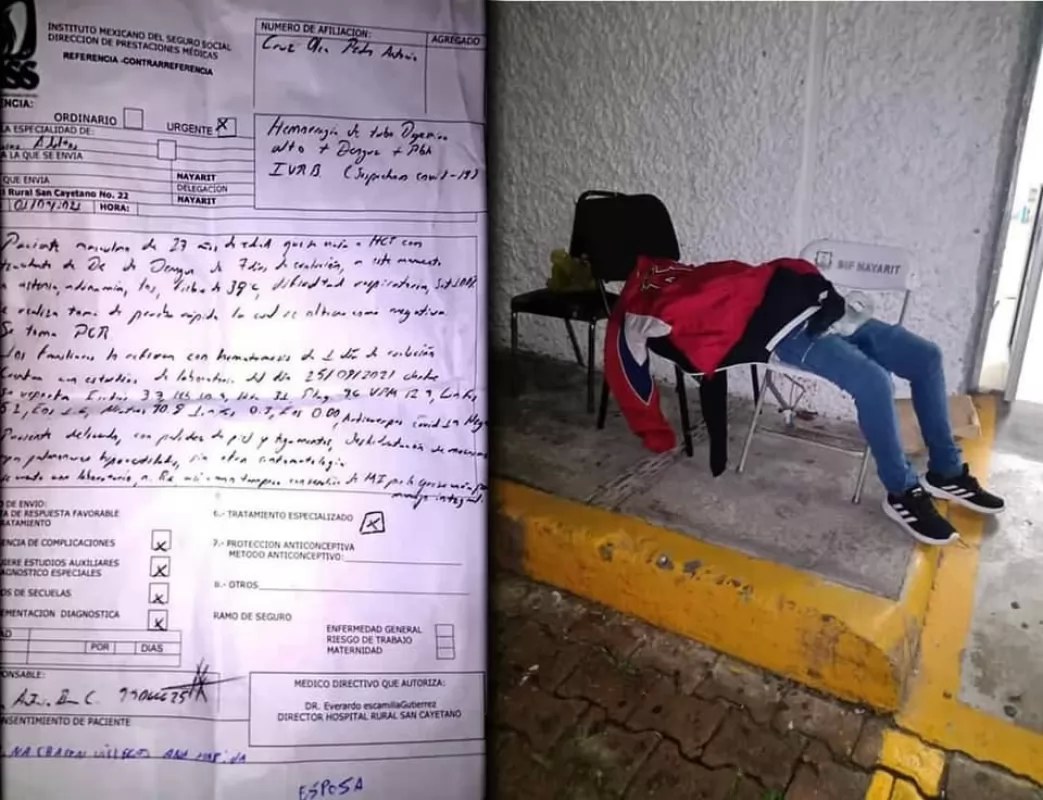

Investiga CDDH fallecimiento de joven afuera del Hospital Civil de Tepic

Colapso hospitalario en Nayarit; Reportan 25 fallecimientos y 366 nuevos casos